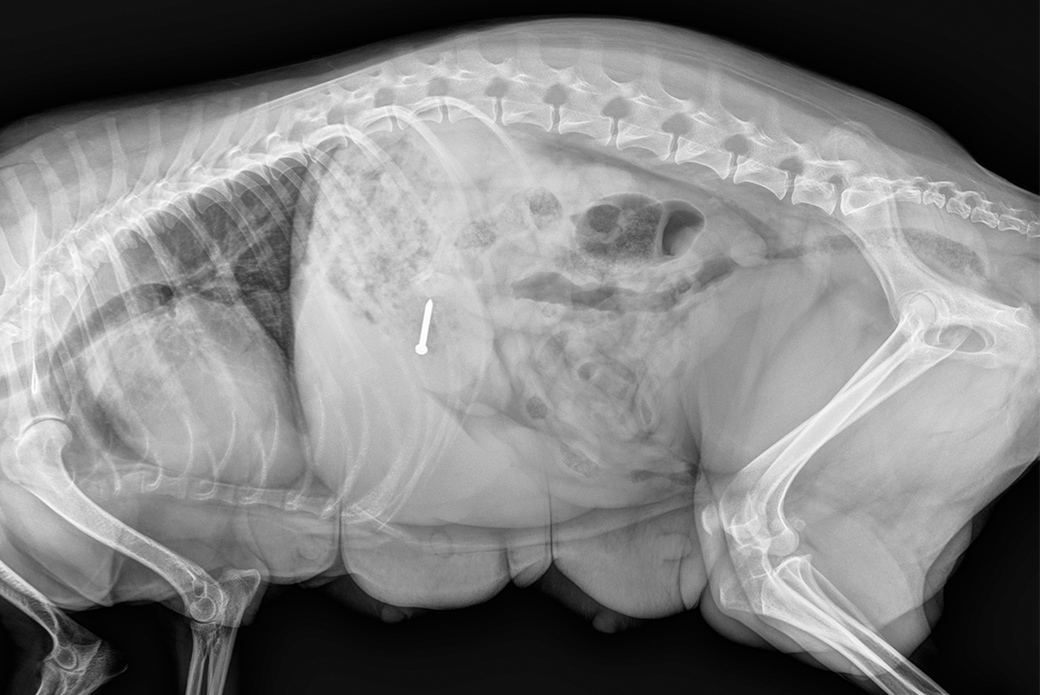

An X-ray soon revealed the source of the problem: A screw was lodged in Sasha’s stomach.

Though no one knows the exact source of the screw, Dr. Gilbert says it could have come from a piece of furniture, and as Sasha started to play with it, she accidentally swallowed it.

Dr. Gilbert surgically removed the screw from Sasha’s stomach, as well as some foreign plastic material. She was also spayed.